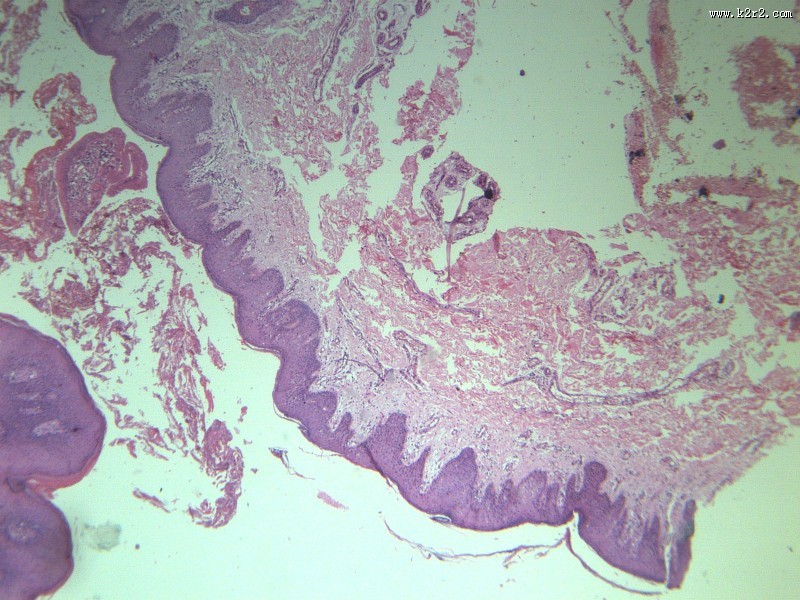

乳头状瘤 - 第1张

乳头状瘤

图集中 / 共有 12 张图片

papilloma of papilla